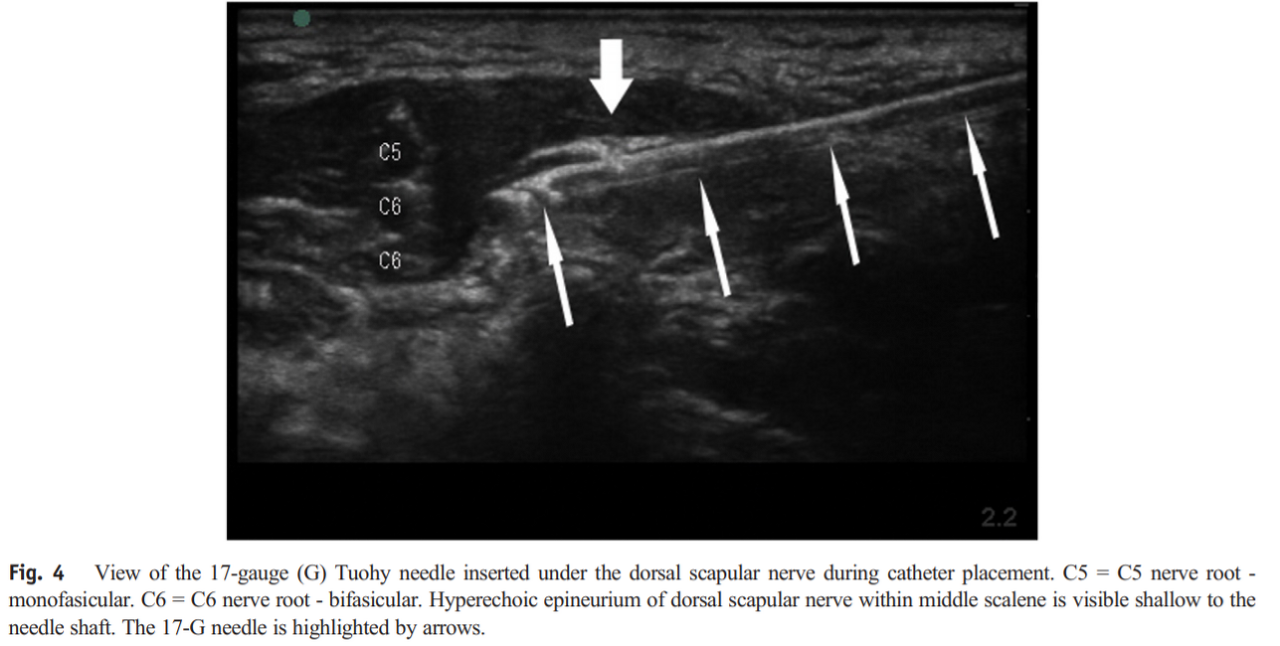

- Auyong, D. B., & Cabbabe, A. A. (2014)

Auyong, D. B., & Cabbabe, A. A. (2014). Selective blockade of the dorsal scapular nerve for scapula surgery. Journal of clinical anesthesia, 26(8), 684-687.

IF = 6.039, SJR Q2

- Treatment

- A posterior inplane approach was used by advancing the needle towards the dorsal scapular nerve traversing the middle scalene muscle (Fig. 4). Ten mL of 0.5% bupivacaine was injected around the nerve using direct visualization for placement of the needle (21-gauge block needle). The patient underwent general anesthesia during the 3.5-hour case, then was brought to the recovery room awake with a pain score of 2 on an 11-point scale.